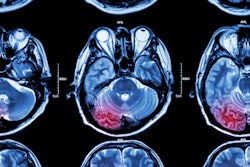

4D ASL angiography demonstrates the feeding arteries and nidus of a cerebral arteriovenous malformation. Image courtesy of Dr. Rolf Jäger.

4D ASL angiography demonstrates the feeding arteries and nidus of a cerebral arteriovenous malformation. Image courtesy of Dr. Rolf Jäger.Dr. Bettina Baeßler, an associate professor of radiology at the University Medical Center Mannheim, Germany, presented alternatives to gadolinium-based contrast agents for cardiac and prostate applications. Replacing gadolinium in these areas can be harder than in the brain.